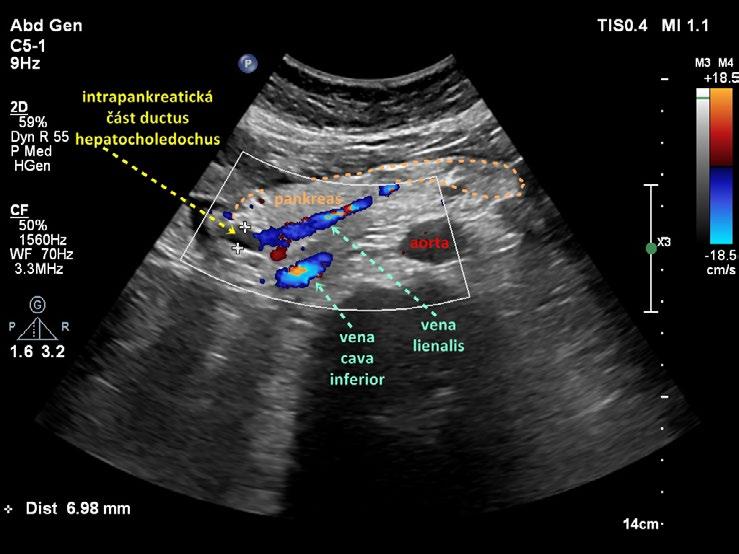

Obr. 1.24 Intrapankreatická část ductus hepatocholedochus

Obr. 1.26 Intrapankreatická část ductus hepatocholedochus podélně